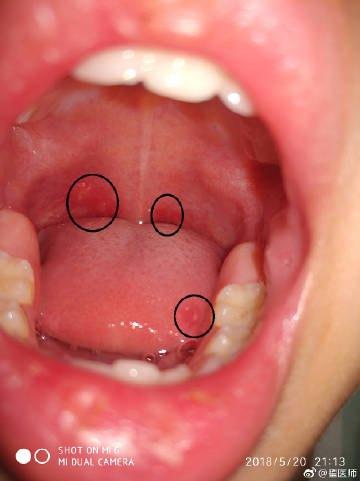

1、疱疹、溃疡:一般在孩子发烧的1—2天之内,孩子的咽喉部会有灰白色的小疱疹,随后这些疱疹会爆开形成溃疡,呈化脓性的白斑。

除了孩子的咽喉部之外,软腭、舌头等其他口腔部位也会出现这些疱疹和溃疡,由于这些病症非常的疼痛,有些孩子会有不愿意吃饭的情况,严重的也会出现呕吐、厌食的情况。